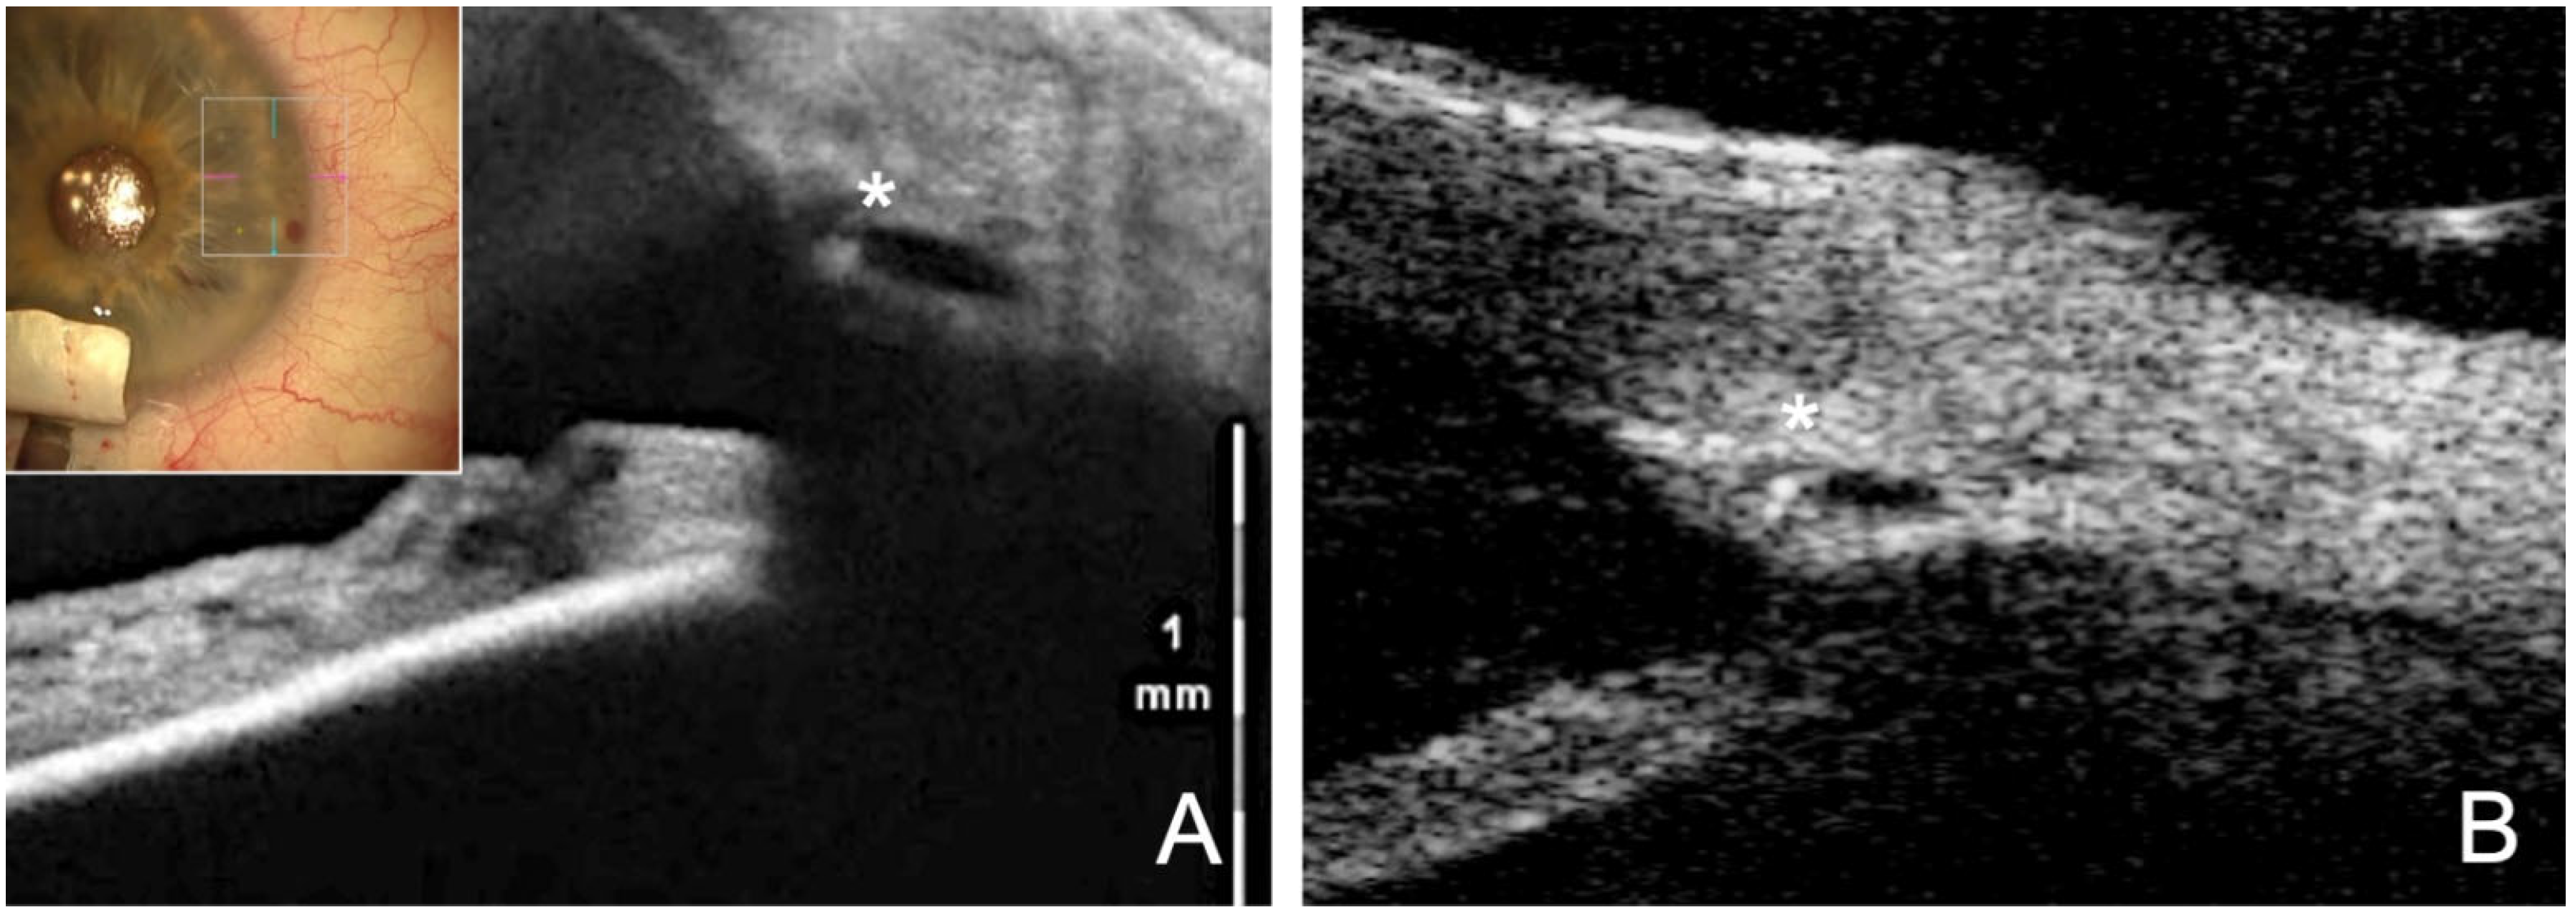

- The SC is probed using a microcatheter (iTrack 250, Ellex Inc., Eden Prairie, MN, USA) for dilatation of the ostia and lumen of SC, and the adjacent collector channels using a viscoelastic. This effect dilates the canal to almost triple its original size, making it easily visible in the ultrasound biomicroscope (UBM) 50 MHz (Figure 1A).